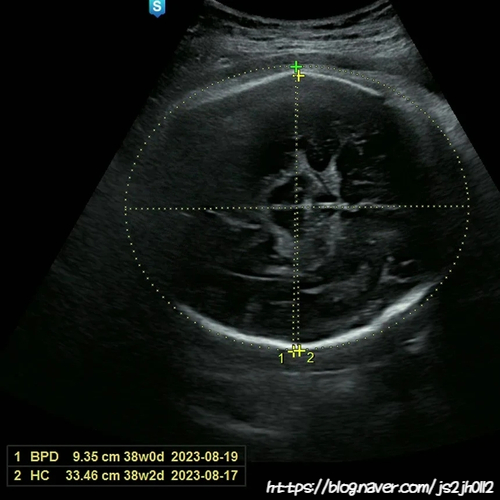

38W주차 진료 때, 양수를 측정했는데 양수량이 37W보다 많이 줄어있었어요ㅠ 선생님께서 유도분만을 시도...

임신 37W

임신 37주차 태동이 조금 약해짐 (한번 움직일때 움직임이 커짐) 하루에 몇번씩 딸국질함 골반쪽이 아픔 소...